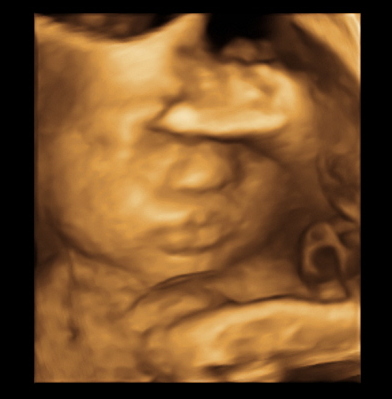

Just got back from my weekly ultrasound and 2 week doctor appointment. Everything still looks great for the both of us. She even flipped back head down from last week. We got some cute shots of her. Here are a few: (I love the one of her sticking her tongue out)

Had a 32 week ultrasound today to check the distance of my placenta to my cervix because it was too close at my 20 week scan. But, thank goodness, as my uterus stretched, my placenta moved up so I'm safe from a scheduled c-section! Woohoo! Also, everything else with baby looked good. He's head down, which means I've been rubbing and talking to his BUTT for the past couple weeks. Best part was the tech got us a couple 3D pics which we didn't expect. He definitely has daddy's flat bridge nose. him.